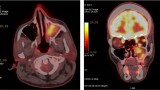

Diagnostyka obrazowa zatok staje się coraz bardziej istotna dla lekarzy dentystów, którzy posiadają w swoich gabinetach aparaty tomografii stożkowej (CBCT). W zależności od wielkości pola obrazowania w CBCT są widoczne fragmenty zatok szczękowych aż po całe zatoki szczękowe, a w badaniach o największym polu obrazowania wszystkie zatoki oboczne nosa, podobnie jak w badaniu medycznej tomografii komputerowej (TK). Z tego względu celem pracy jest przedstawienie najważniejszych zmian patologicznych zatok szczękowych, z którymi może się spotkać lekarz stomatolog, opisując badania tomografii stożkowej (CBCT).